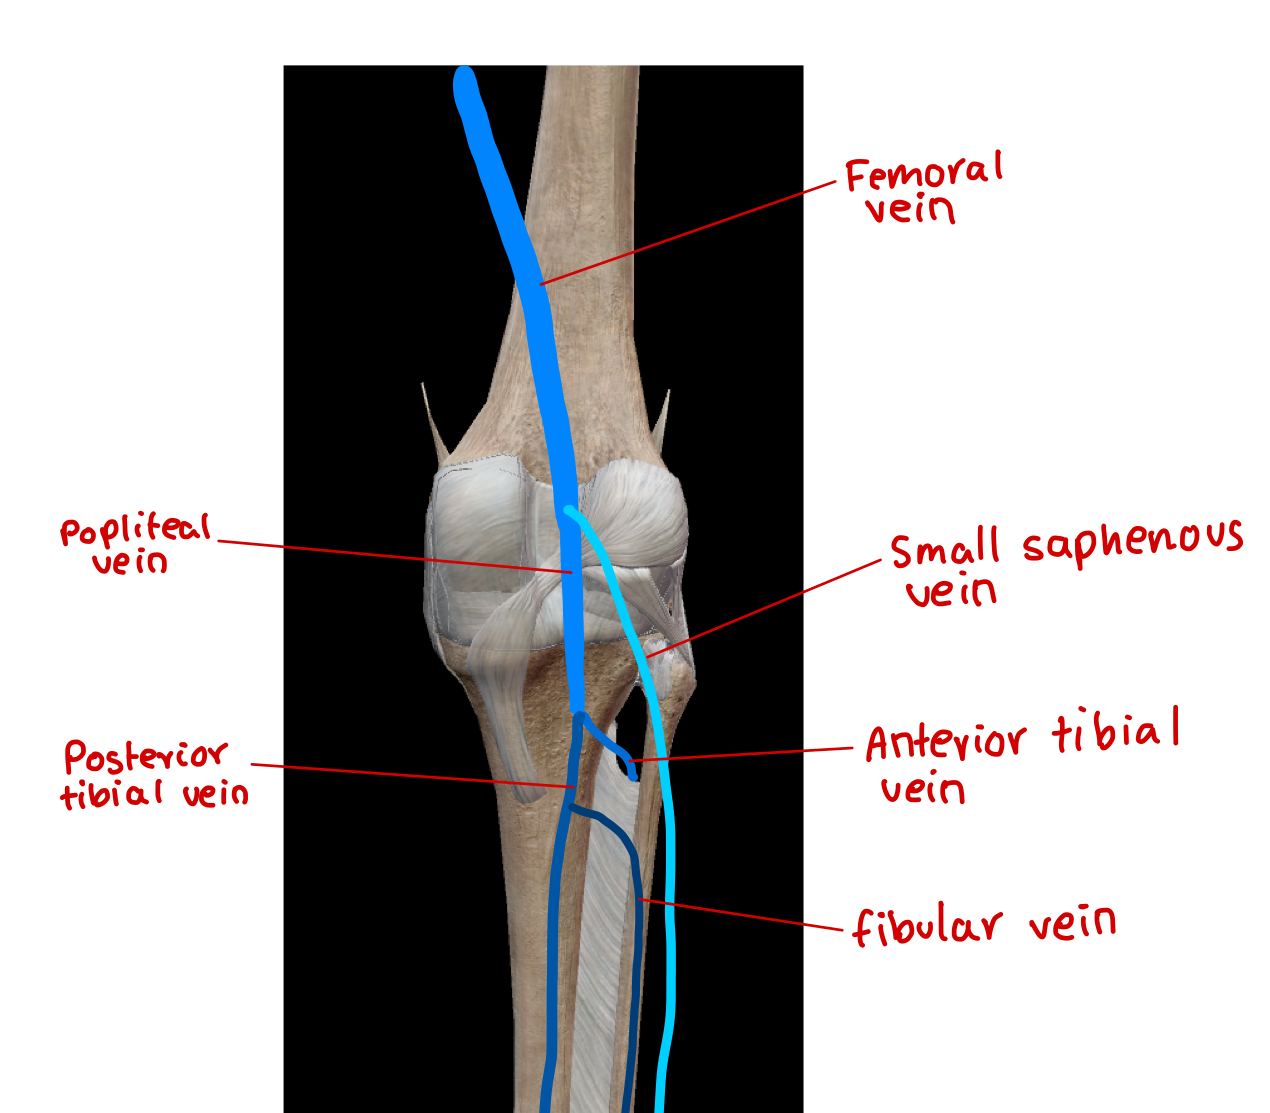

label the veins in the hip region

label the vein in the lower limb